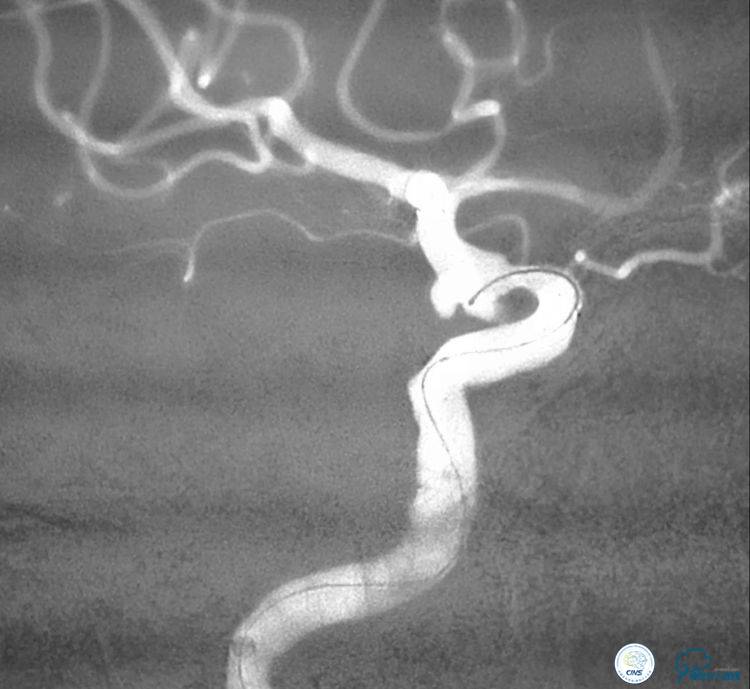

▼将3米的微导丝超选择到大脑中动脉M2以远。

▼选择3×9mm Getway球囊进行扩张。

▼扩张后狭窄明显改善。

▼释放4.5x20 Neuroform支架。

▼将微导管超选择到动脉瘤腔内。

▼2个微导管到位。